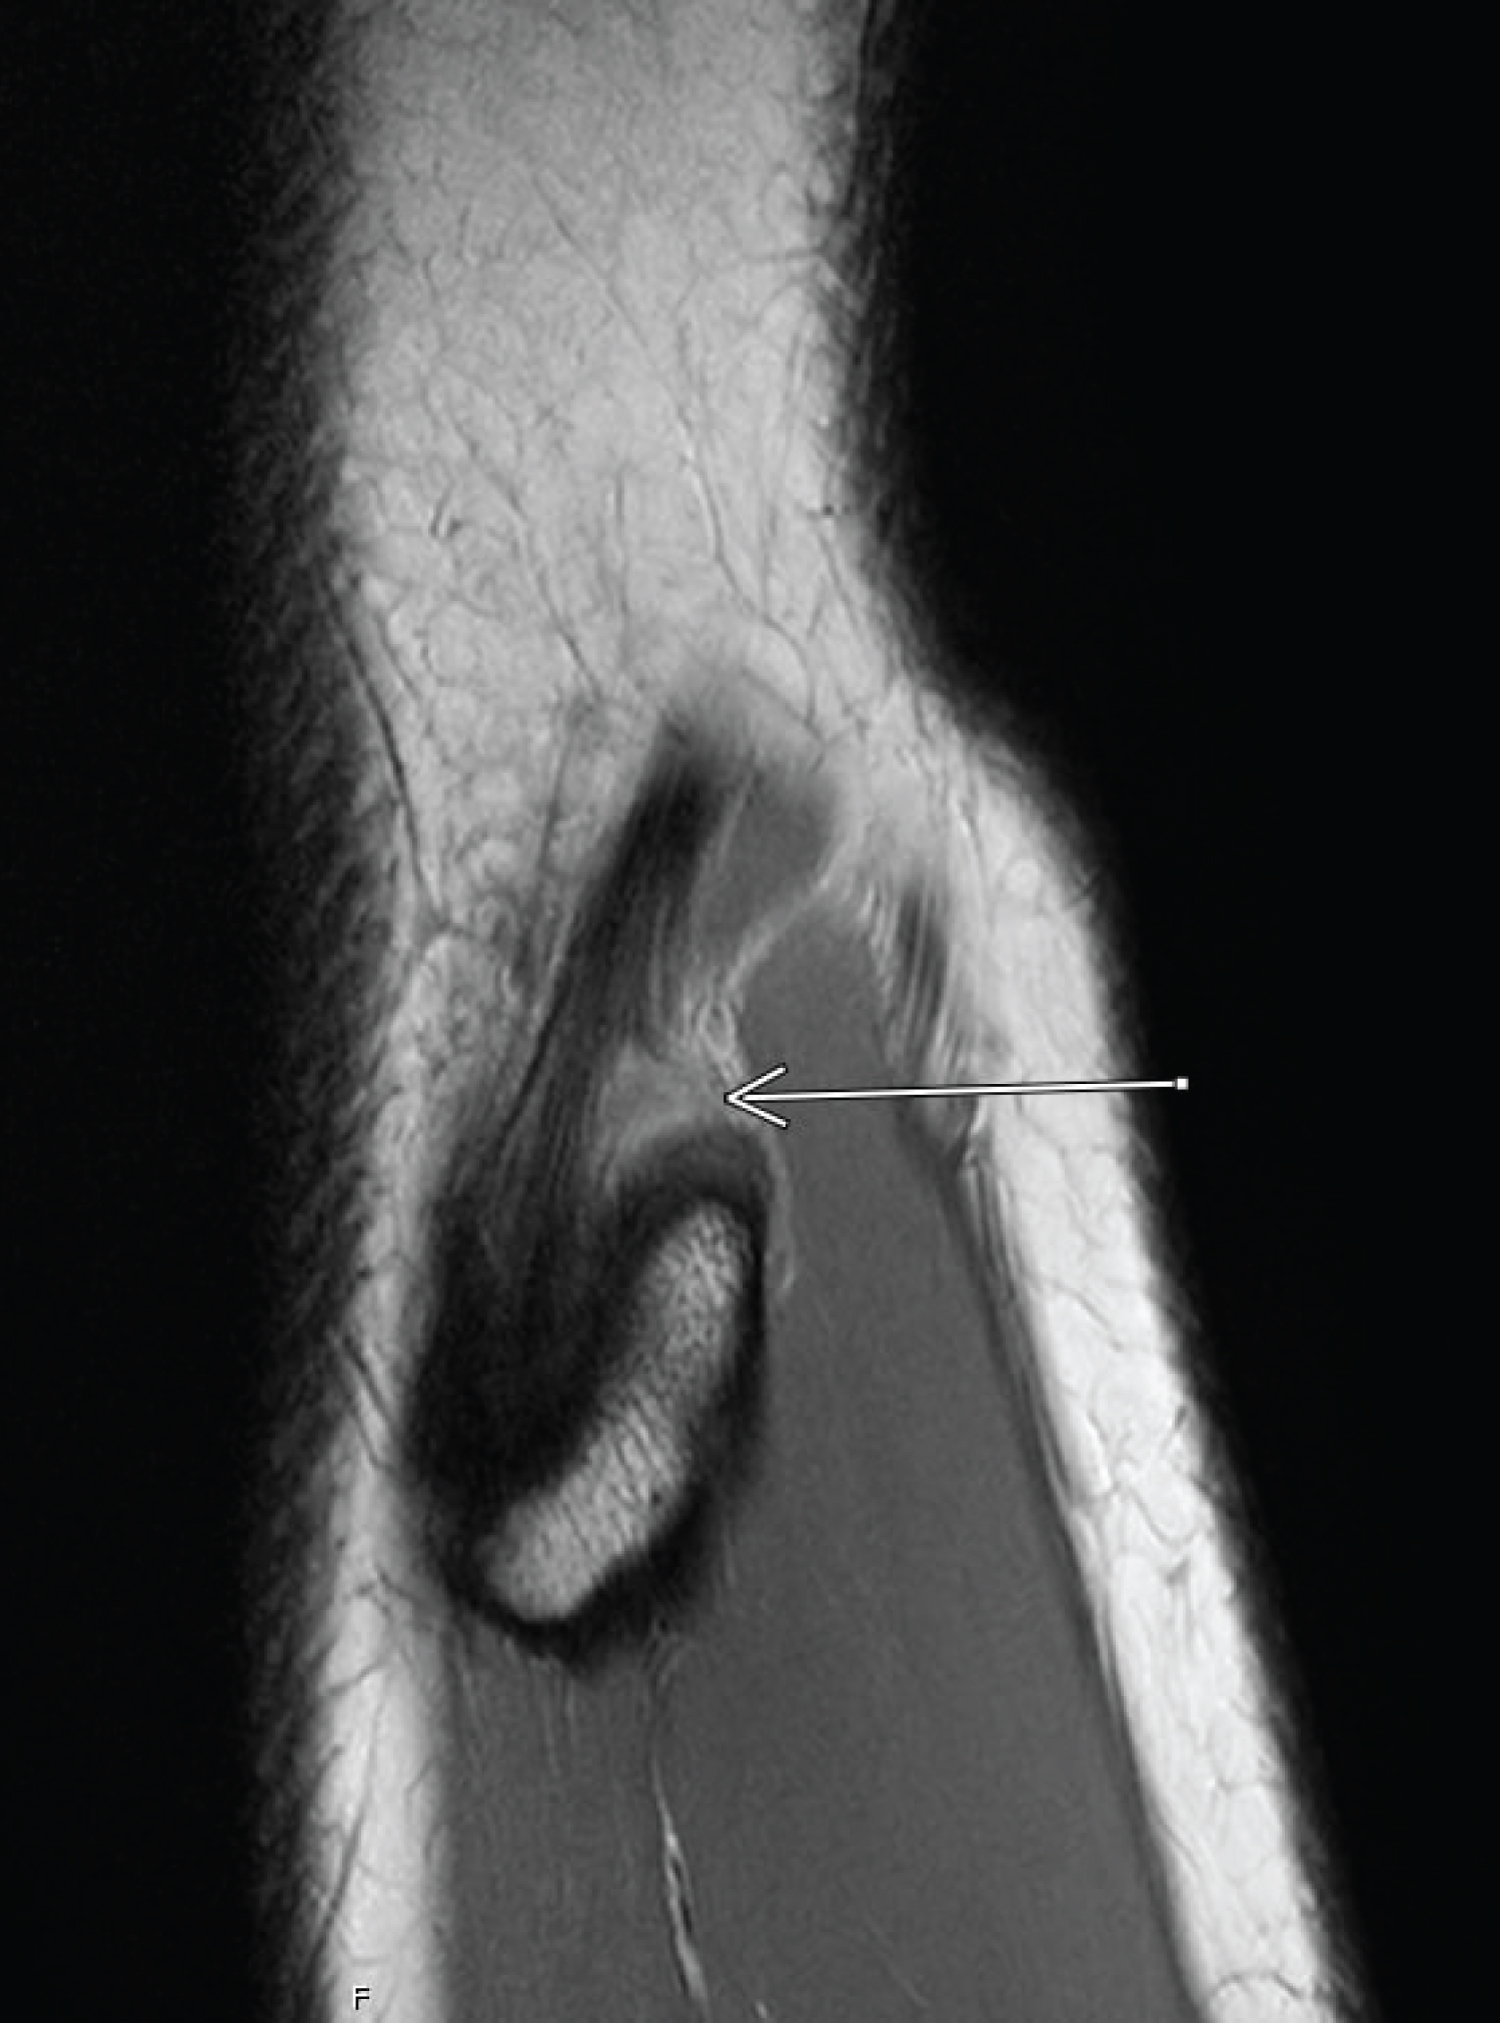

As suspected based on the clinical findings, MRI confirmed pathology involving the biceps femoris tendon, albeit a full thickness partial width tear of the posterior fibular attachment involving approximately 30% of the tendon width. This was associated with a bleed extending superior to the musculo tendinous junction (Figure 1 and Figure 2).

Figure 1: Sagittal PD-weighted SPAIR (SPectral Adiabatic Inversion Recovery) image of partial width tear of the posterior biceps femoris fibular attachment. View Figure 1